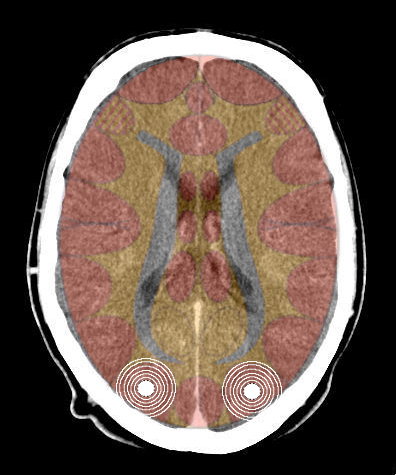

- Requisiti: Si è in costellazione schizofrenica quando due attivazioni colpiscono i due emisferi cerebrali di uno stesso livello:

- le due emiparti del tronco cerebrale;

- i due emisferi cerebellari;

- i due emisferi cerebrali (midollo e/o corteccia).

- NON È COSTELLAZIONE quando due attivazioni interessano due livelli cerebrali differenti, anche se occupano i due emisferi.